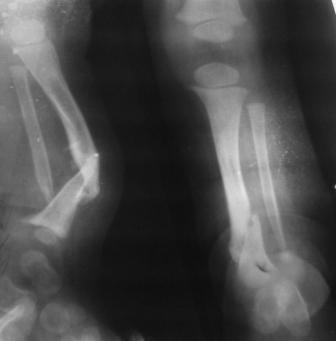

Глубокоуважаемые коллеги женщины! Поздравляем с праздником ВЕСНЫ, Международным женским днем - 8- МАРТА, здоровья , благополучия и успехов во всем! Ребенок 1г, мальчик, от первой беременности, родился без патологии весом 4кг, родители травму исключают, постепенно заметили деформацию н/з голени, которая начала увеличиваться . Брак родственный. Об-но; имеется угловая деформация открытым углом кзади на уровне н/з голени, ригидная , коррекции поддается мало. Функция коленного и г/с суставов не нарушены. Уважаемые детские ортопеды! Почему такое упорное молчание ортопедов! Я искреннее прошу прошения , если можно , мы нуждаемся в Ваших советах! План лечения; этапное, дистракционный аппарат, коррекция деформации, остеотомия в/з б/б кости, удлиняющая дистракция в обл остеотомии с одновременной компрессией в обл псевдоартроза и наблюдение , дальше по обстоятельству Вопросы; . 1. В каком возрасте можно начинать лечение, какие еще варианты лечения? 2. На Р-грамме как будто имеется недоразвитие дистального эпиметафиза м/берцовой кости, тогда что можно делать? С уважением Абдурашид.

Случай, который я представляю, был сделан мной около 20 лет назад в Кургане.

Женщина 28 лет, пошедшая 13 предыдущих оперативных вмешательств по-поводу ВПБ имела 9 см. укорочения.

На первом этапе аппаратом Илизарова закрыто устранена деформация голени.

На втором этапе произведёно освежение краёв костных фрагментов б/б и м/б костей с приданием проксимальному фрагменту б/б кости впалой, а дистальному выпуклой формы, открытие канала проксимального фрагмента и погружной остеосинтез, а также остеотомия б/б кости в в/3 и м/б кости на границе с/3 и н/3 голени. Больной проводился одновременный бифокальный компрессионно-дистракционный остеосинтез. Достигнуто 11 см. удлинение и сращение ВПГ.

Срок лечения 11 месяцев. Наблюдение 2 года.